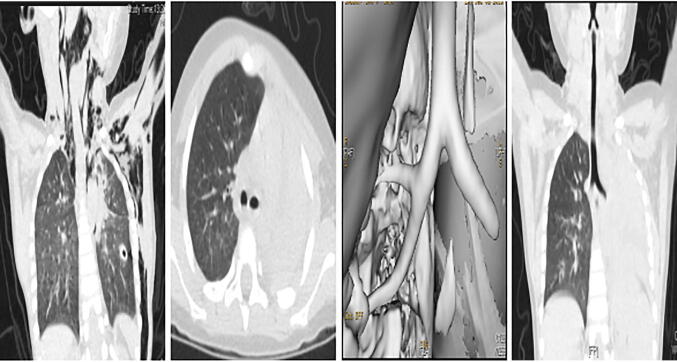

After admission to our hospital, interruption of the bronchus and atelectasis of the diseased side was found in eight patients by chest CT with three-dimensional reconstruction (Fig. 2). Interruption of the bronchus was found in all cases by fiberoptic bronchoscopy (Fig. 3). There were six cases of left main bronchus rupture, one case of right main bronchus rupture and one case of right middle bronchus rupture in the group. Injuries other than those involving the bronchi and lungs included six cases of rib fracture, two cases of limb fracture, two cases of abdominal closed injury, two cases of craniocerebral injury, one case of clavicular fracture, and one case of spinal injury.

Fig. 2.

Preoperative CT image

In this group, the time from trauma to diagnosis was 1–52 days (median time 27.5 days). Four cases (50%) were type I bronchial rupture, and four cases (50%) were type II bronchial rupture. One case was treated by an emergency operation. Another case was not treated with emergency bronchial rupture surgery due to another serious comorbid injury, and bronchial rupture surgery was performed 1 week after the condition stabilized. The rest performed bronchial rupture surgery at least 2 weeks after trauma. The distance between the bronchial stump and the trachea carina in all patients was approximately 2 cm. The postoperative ventilator-assisted breathing time was 8.5–129.4 h (median time: 101.4 h). There was no bronchopleural fistula after the operation. Seven patients received bronchial end-to-end valgus anastomosis, and one received right middle lobe lobectomy. There were no deaths in this group, and all patients were cured and discharged. Follow-up was conducted for 3 months to 2 years, and the patients subjected to the operation showed mild bronchostenosis within 2 weeks after trauma upon CT examination. The other six cases showed moderate bronchostenosis (Fig. 4), and they were followed-up for observation.